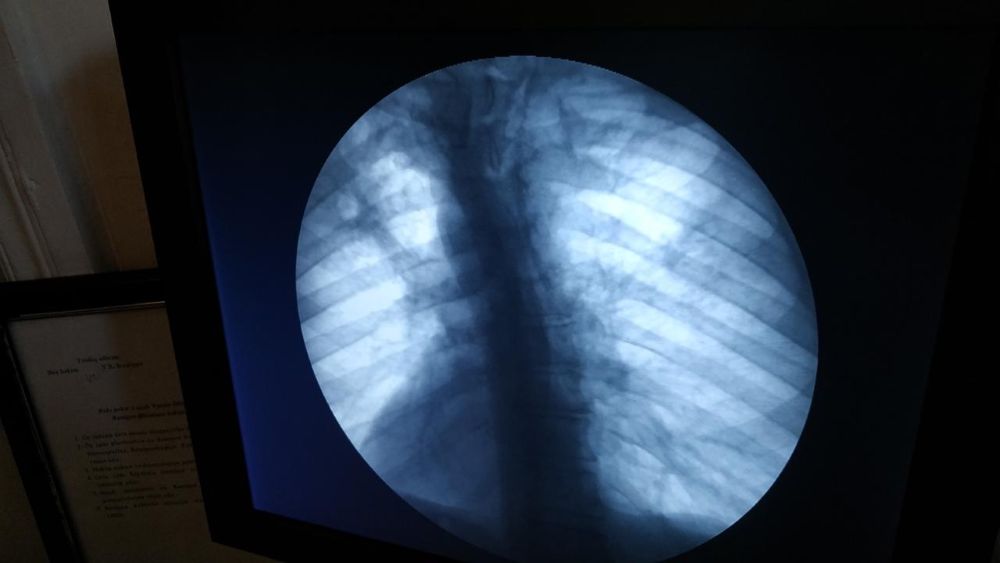

Ə.Əliyev adına Azərbaycan Dövlət Həkimləri Təkmilləşdirmə İnstitutunun ftiziatriya kafedrasında müdavimlərin praktiki bacarıqlarının inkişafına xüsusi önəm verilir və tədris prosesinə ən müasir diaqnostik texnologiyalar inteqrasiya olunur. Kafedranın klinik bazasında tətbiq edilən “Shimadzu Flexavision SF” rəqəmsal rentgen kompleksi vərəm və digər torakal patologiyaların yüksək dəqiqliklə diaqnostikasına şərait yaradır. Bu kompleks 1024×1024 piksel icazəli PZS-matris ilə təchiz edilmiş, teleidarəetməli universal rentgen sistemidir.

Cihazın köməkliyi ilə davamlı rentgenoskopiya, aşağı dozalı impuls rentgenoskopiya, ekran-sənəd qurğusuna rentgenoqrafiya, tək və seriyalı çəkilişdə rəqəmsal rentgenoqrafiya, rəqəmsal subtraksion angioqrafiya aparmaq mümkündür. Avadanlığın avtomatik ekspozisiya nəzarəti, anatomik proqramların seçimi, aşağı dozalı filtrasiya sistemi və görüntülərin dərhal konsola ötürülməsi tədris prosesini daha funksional edir. Cihazın kompakt dizaynı və şaquli çəkiliş imkanları real klinik şəraitdə daha geniş praktik fəaliyyətə imkan verir.